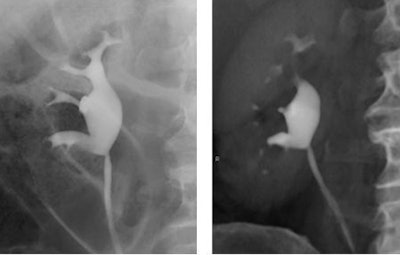

![]() |

| Retrograde pyelogram versus IVU. Left, normal right retrograde pyelogram. Right, single volume-rendered CT image obtained during 64-channel CTU. Images courtesy of Dr. Terri Vrtiska, Mayo Clinic, Rochester, MN. |

A single breath-hold split-bolus technique was designed to maximize acquisition speed while yielding isotropic (0.4-mm) resolution, Vrtiska said. The scans were performed in 12 patients (seven men and five women, ages 30-78) with a history of hematuria (n = 7) or transitional cell carcinoma (n = 5).

The single-breath-hold protocol, combined with MIP and VRT postprocessing techniques, provides 0.4-mm isotropic CT, enabling the visualization of urothelial pathology routinely seen on traditional IV urography, she concluded.